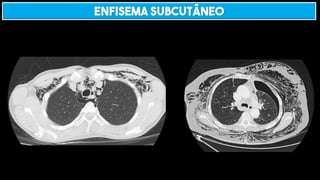

ENFISEMA SUBCUTÂNEO

TRAUMA É CAUSA MAIS COMUM!

OUTRAS CAUSAS IMPORTANTES:

Pneumotórax

Pneumomediastino

Enfisema intersticial pulmonar

Perfuração de víscera oca

Fasciíte necrotizante